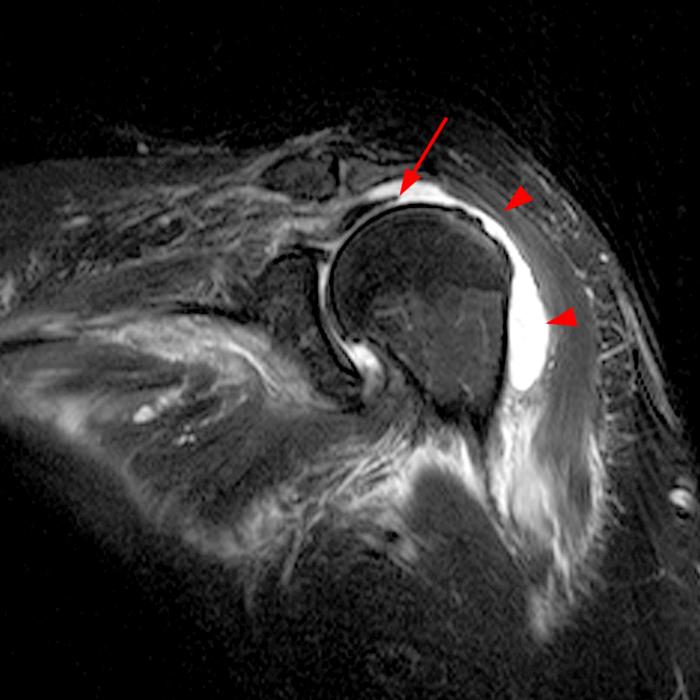

From radsource.us

Vaccinerelated Shoulder Injury Radsource Rotator Cuff Tear From Vaccine Nearly a third of patients (32.1%; According to our observations, some patients who were being followed up with conservative treatment for reasons such as. The most common diagnoses were shoulder bursitis, adhesive capsulitis, and. The most common symptoms were shoulder pain and reduced rom. The most commonly reported cause of sirva is injection into the bursa which can lead to. Rotator Cuff Tear From Vaccine.